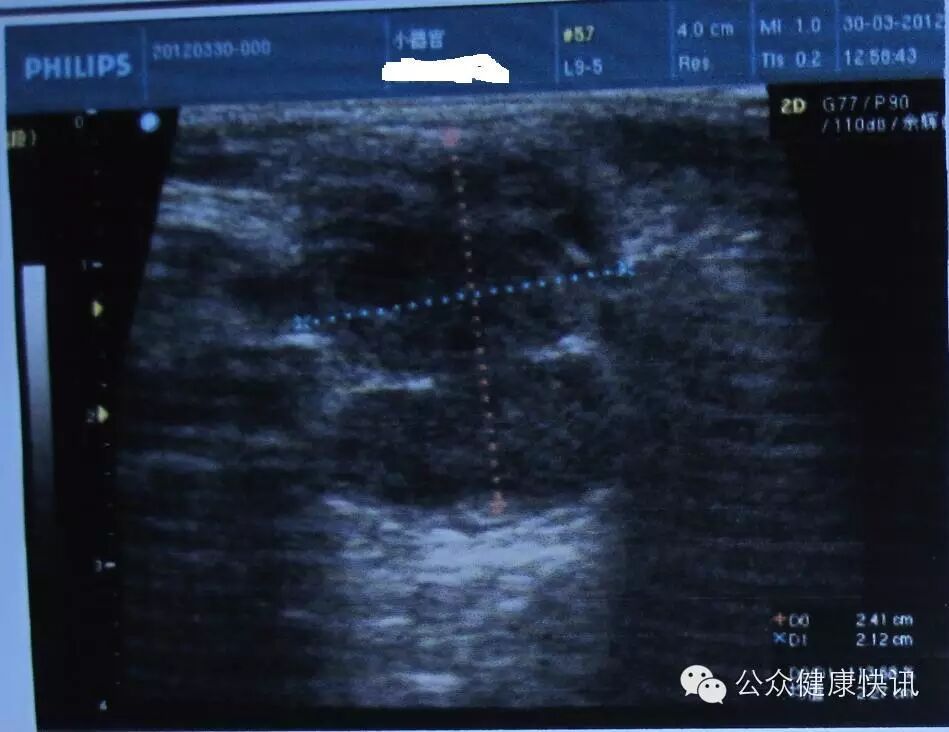

这是肿块的B超检查